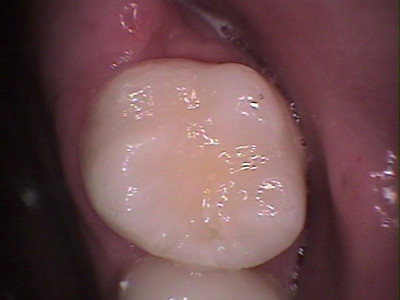

Después